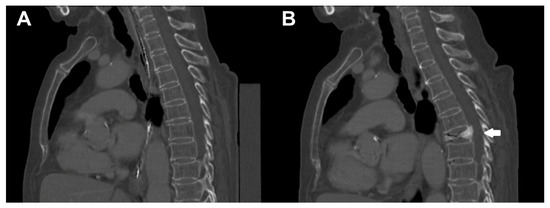

Extraction of vBMD as well as calculation of FEMs, load, and displacement were possible for all enrolled patients. Table 2 shows the mean values and ranges of these parameters for the whole cohort. Figure 2 depicts an illustrative patient case.

Figure 2. Illustrative patient case. This figure depicts sagittal reformations of the spine of a 78-year-old female patient (A) at baseline and (B) during follow-up imaging by multi-detector computed tomography (MDCT). During the interval of 8 months between baseline and follow-up scanning, the patient sustained an incidental osteoporotic vertebral fracture (VF) of T7 (white arrow).